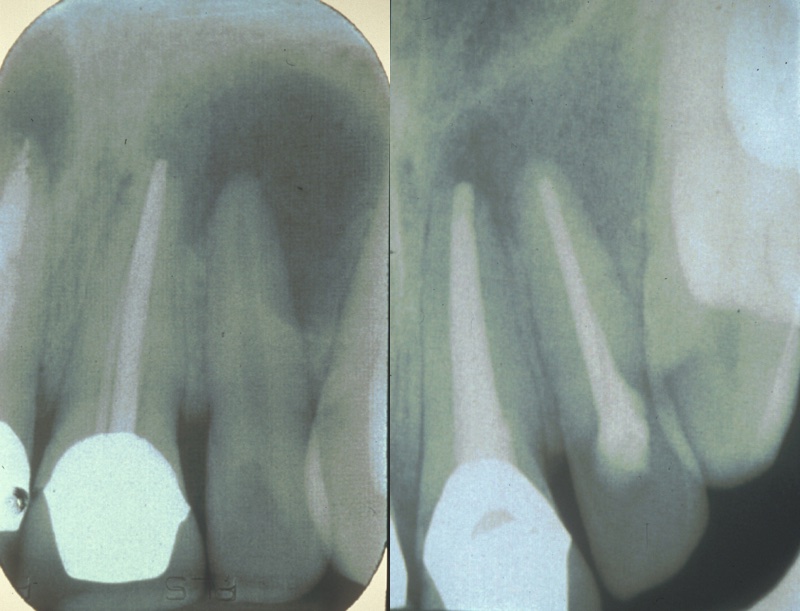

Figure 1 Left: large periapical radiolucency associated with upper left second incisor (UL2); right: lesion almost completely healed six months after conventional endodontics.